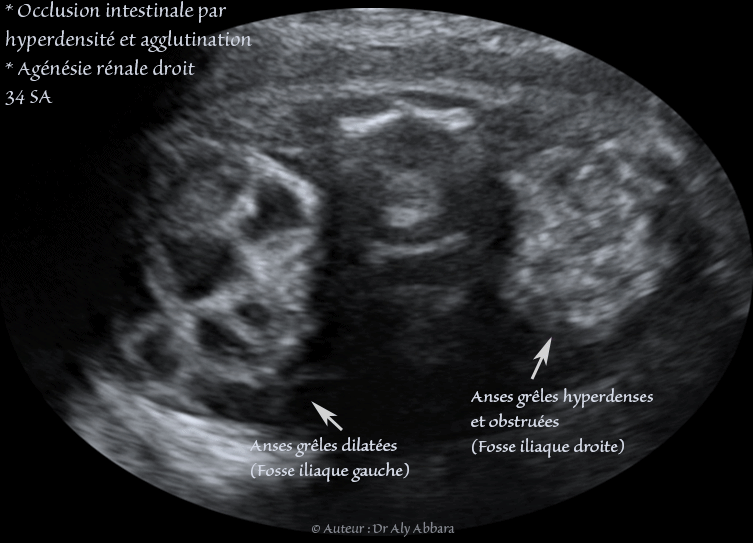

Images échographiques montrant une occlusion intestinale se manifestant par la dilatation des anses grêles et un hyperpéristaltisme.

Cette occlusion intestinale est liée à la présence, dans la fosse iliaque droite, comme on le voit sur ces images, d'un magma d'anses grêles hyperdenses, agglutinées et obstruées.

L'estomac n'est pas dilaté (occlusion digestive basse), mais on note également l’existence de deux anomalies morphologiques associées :